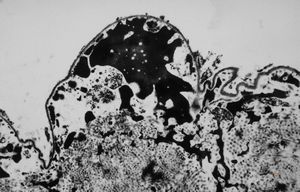

F,49y. | purulent meningitis- meningococcal v.s.

F,49y. | purulent meningitis- meningococcal v.s.

F,49y. | purulent meningitis- meningococcal v.s.